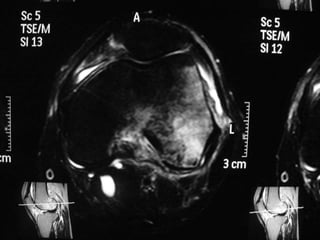

The document presents a detailed case study of a patient with transient osteoporosis of the hip (TOH) and spontaneous osteonecrosis of the knee (SONK) treated at Choithram Hospital & Research Centre in India. Over 20 years, the patient experienced multiple episodes of TOH and SONK with no history of trauma or co-morbidities, resulting in resolutions and recurrences of conditions. The information is intended for orthopedic surgery students and highlights personal experiences and case collections, with a disclaimer regarding content usage and potential controversies.